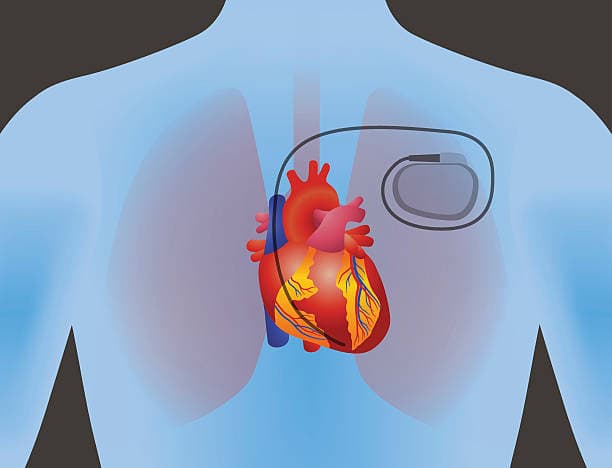

Pacemakers are small, sophisticated electronic devices that play a critical role in maintaining a regular, effective heartbeat in patients whose natural cardiac rhythms are disrupted or insufficient. Essentially, a pacemaker is implanted surgically under the skin, typically just below the collarbone, with one or more thin wires called leads connecting it to the heart. These leads deliver precisely timed electrical impulses that prompt the heart muscle to contract, ensuring it beats at a normal rate and rhythm. This device is especially valuable for individuals suffering from conditions such as bradycardia, where the heart beats too slowly, or various forms of heart block where electrical signals are delayed or obstructed. Modern pacemakers now often include advanced features like rate responsiveness, which adjusts the pacing rate in accordance with a patient’s level of physical activity, and some even offer sophisticated diagnostic capabilities for remote monitoring by physicians. They are available in several types, including single-chamber, dual-chamber, and biventricular devices, each tailored to address specific cardiac conditions. Their batteries, designed to last several years before replacement is required, ensure reliable long-term operation and reduce the need for frequent interventions.

Pacemaker implantation is indeed a surgical procedure, but it is generally not considered major surgery due to its minimally invasive nature. Typically performed under local anesthesia with light sedation, the procedure avoids the risks associated with general anesthesia and involves only small incisions. A small cut is made near the collarbone to create a pocket under the skin where the pacemaker device is placed, and one or more thin leads are inserted through a vein into the heart. Using real-time imaging techniques, the surgeon precisely positions these leads to monitor and regulate the heart’s rhythm, ensuring the device functions as a seamless extension of the heart’s electrical system. The entire process usually takes one to two hours, and thanks to its minimally invasive approach, most patients can return home the same day or after a brief overnight stay for observation.